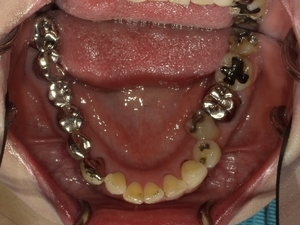

〇ご相談内容:歯並びがよくない〇矯正の種類:マウスピース型矯正「インビザライン」〇治療期間:39週間〇治療費用:44万円(税込)